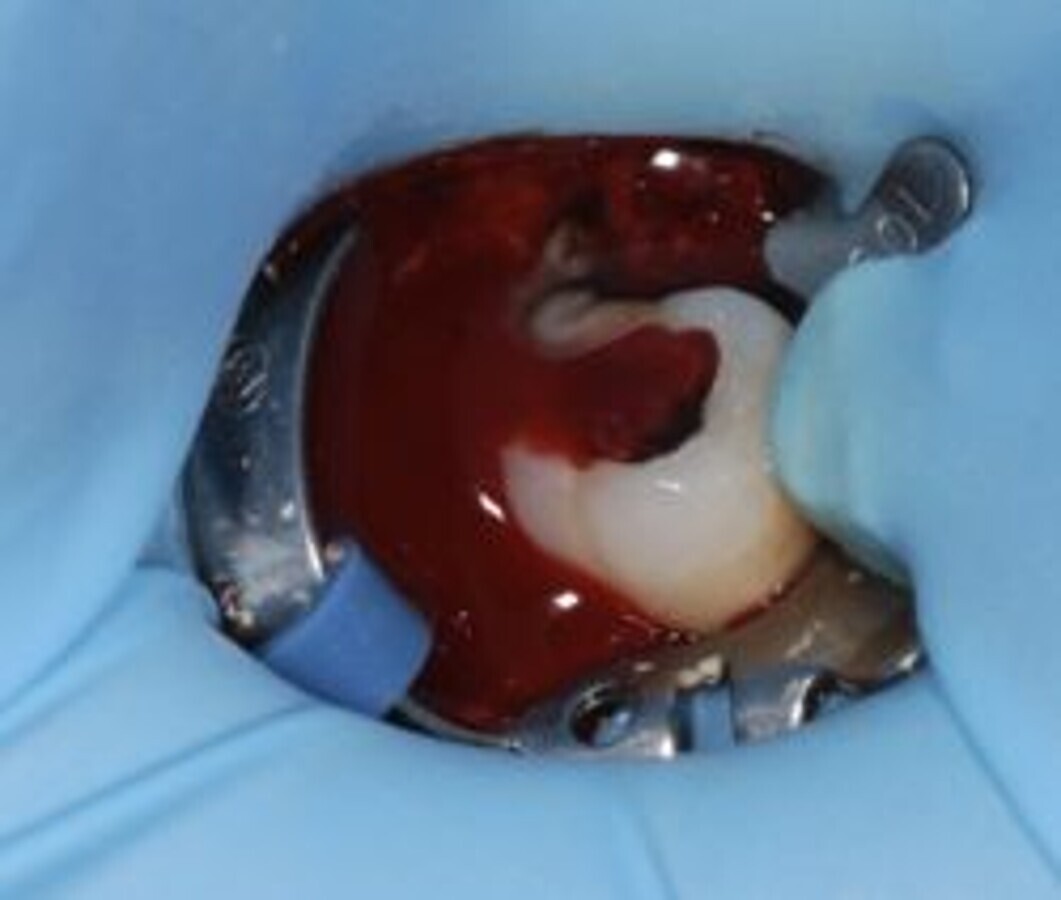

Twee foto’s van een 47 (röntgen en klinisch). Het starten van een wortelkanaalbehandeling is vaak de beste remedie bij acute klachten. FOTO’S: BRAM LAK

Wortelkanaalbehandeling

De richtlijn ‘Endodontische diagnostiek en behandeling’ biedt u op het gebied van de behandeling van acute klachten geen snelle oplossing. Het starten van een wortelkanaalbehandeling is vaak toch de beste remedie. Een goede start van een wortelkanaalbehandeling verdient aandacht en tijd. Mocht u op het moment dat u de patiënt ziet niet de tijd hebben om deze behandeling goed uit te voeren, dan is het voor de patiënt en uzelf beter om die op een later tijdstip te plannen en de patiënt in de tussenliggende periode pijnvrij te houden met adequate pijnstilling. Als alternatief kan er een langwerkend anestheticum (bijvoorbeeld bupivacaïne) toegediend worden. Een te snel en niet zorgvuldig uitgevoerde behandeling is vaak niet effectief en leidt mogelijk zelfs tot meer problemen.